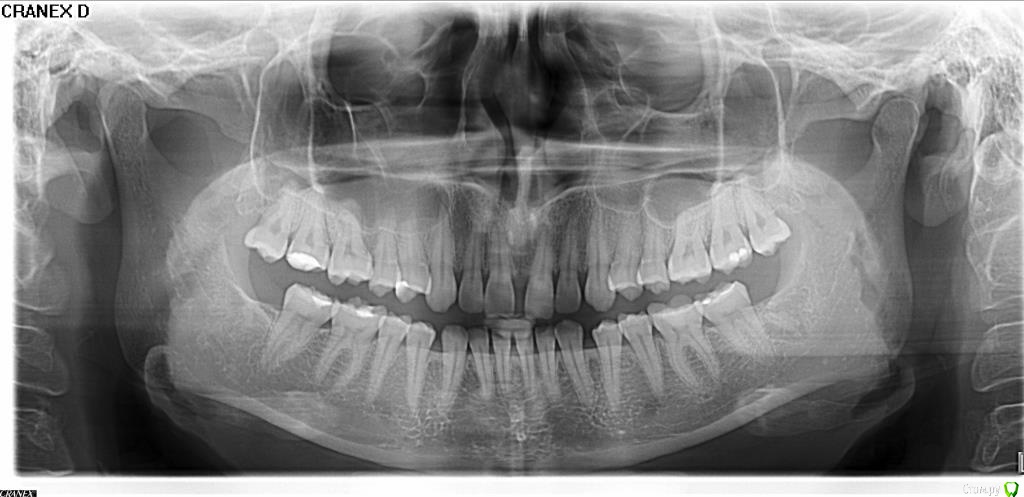

Elena85 Опубликовано 22 декабря, 2015 Поделиться Опубликовано 22 декабря, 2015 Добрый вечер. Уважаемые врачи, подскажите, что это может быть и к какому специалисту мне нужно обратиться.У меня после родов и удаления нижних 8-ок (с двух сторон) появилась сильная боль в десне, после еды твердой или волокнистой пищи. Не могу вообще есть мясо, рыбу, яблоки. Если попадает пища между 7 и 8 зубами вверху (с двух сторон), то идет резкая боль, как-будто клин между зубами вставили и раздвигают их, после прочистки зубов зубной нитью, боль становится еще острее, потом через некоторое время боль становится пульсирующей и сохраняется несколько дней. После еды твердой пищи боль распространяется по всей челюсти, кроме передних зубов. Нижние зубы тоже начинают болеть в этой же области, т.е.7-ки, а потом боль так же идет по всей челюсти. Обращалась к стоматологу - говорит, что с зубами все в порядке, только в 8-ах есть небольшие дырочки, но они не могут давать такую боль. По панорамному снимку - тоже все в порядке, но боль есть и никуда не уходит. Бывает, что даже КЕТАНОВ не помогает. Ссылка на комментарий